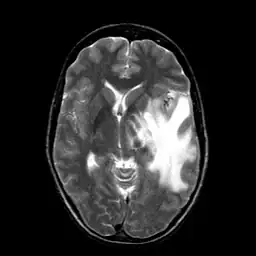

I am currently working on translating Matlab version active contour to OpenCV. It seems that OpenCV has its own version of active contour but deprecated then. I am curious about how different between this version with Matlab version. So I did a comparison experiment. Given a MRI brain image and an initial boundary , I applied both Matlab and OpenCV version active contour to segment the white matter in brain.

For both Matlab and OpenCV, I choose gradient(edge) method of active contour. I then labeled the results on the image. The red curve is initial boundary while the green curve is final boundary.

I attached the original image and mask in case someone wants to repeat the test.